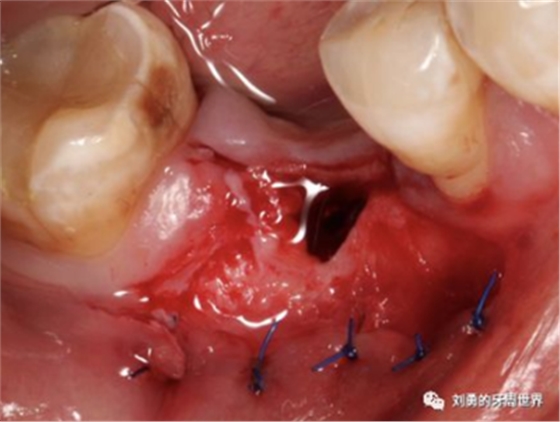

比如下面兩張圖就分別是縫合和剪掉的方法: